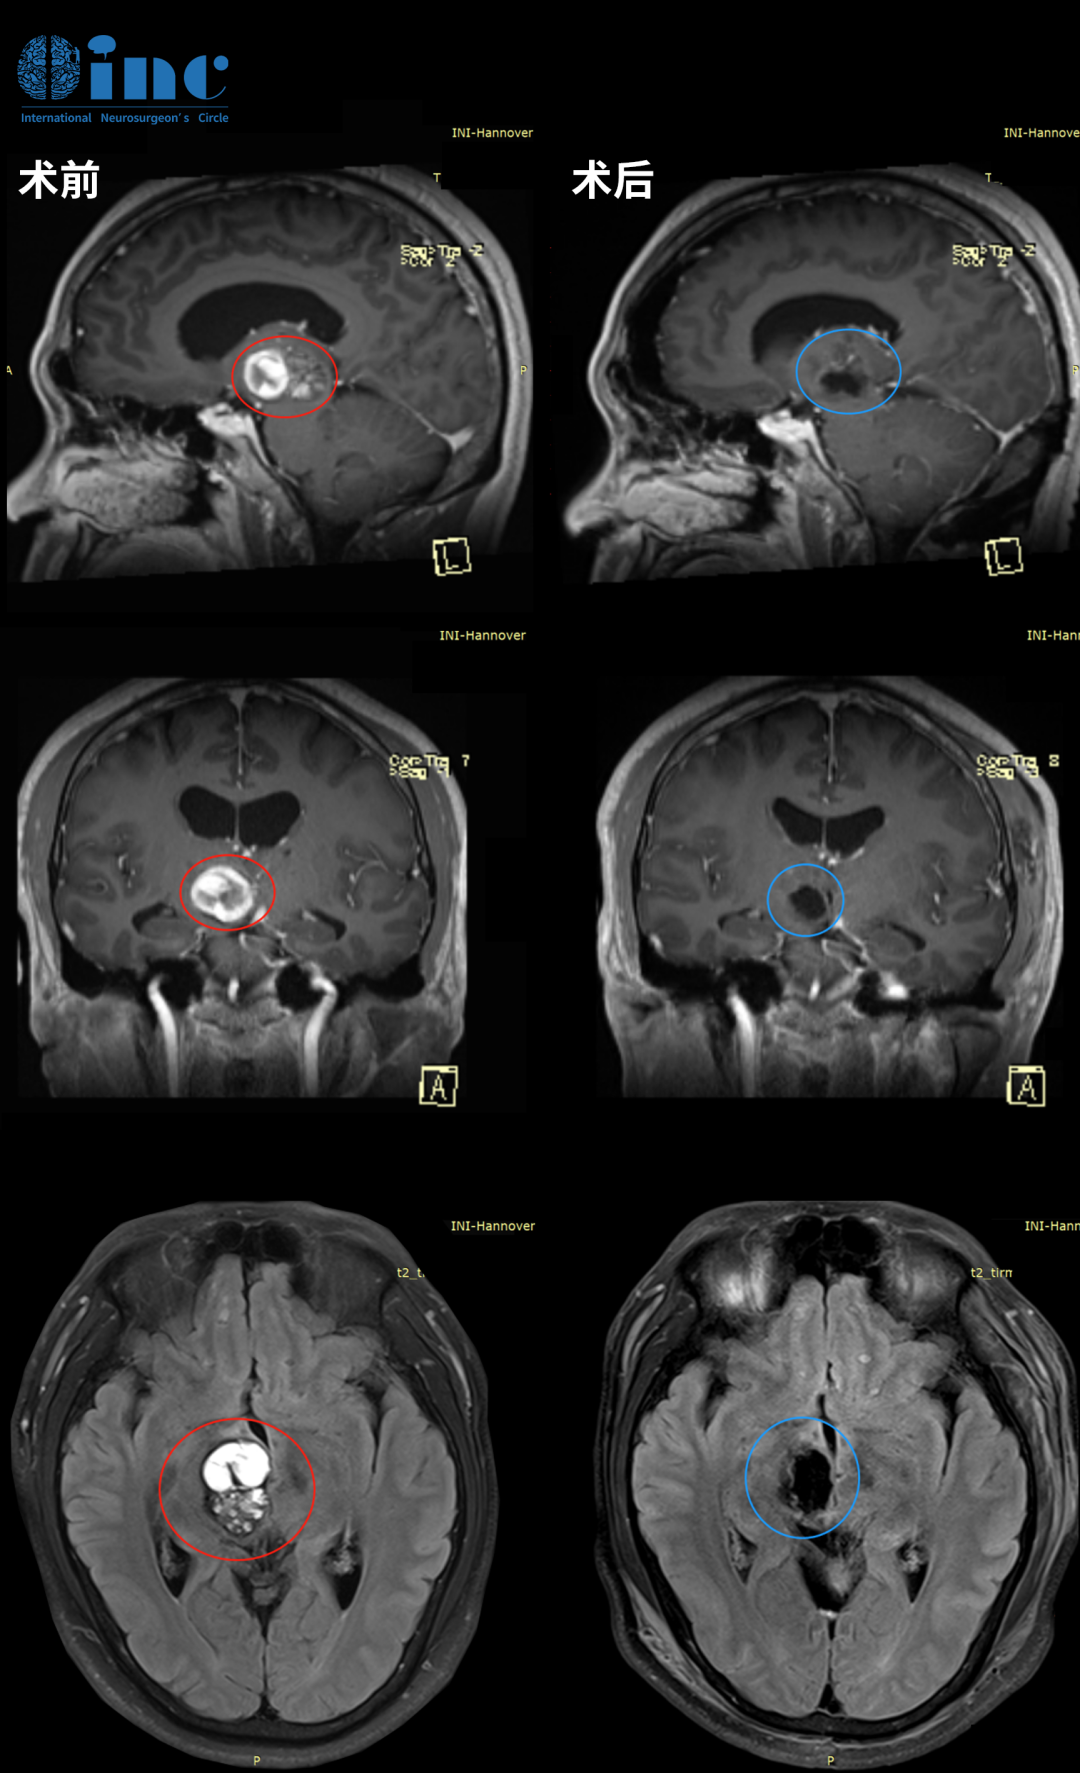

這是一例多年前曾行嗅神經(jīng)母細(xì)胞瘤切除術(shù)的患者,術(shù)前軸位(A)與冠狀位(B)T1加權(quán)釓增強(qiáng)MRI顯示沿右側(cè)蝶骨大翼新出現(xiàn)的均勻強(qiáng)化病灶。經(jīng)右側(cè)改良外側(cè)眶切開眶-顱入路完整切除病灶后,術(shù)后軸位(C)與冠狀位(D)T1加權(quán)釓增強(qiáng)MRI顯示病灶已完全切除,患者神經(jīng)功能完全恢復(fù),無(wú)新增神經(jīng)功能缺損。

圖.改良外側(cè)眶切開術(shù)案例分享